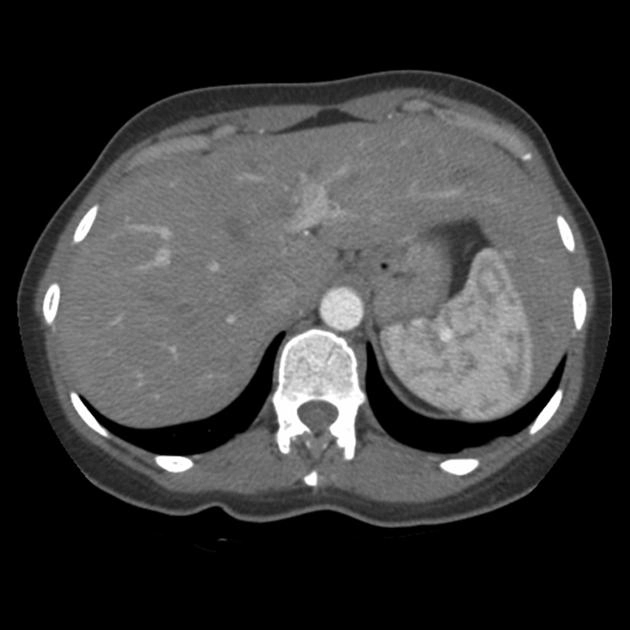

Nang lách (Splenic Cyst)

U máu lách (Splenic hemangioma)

U mạch bạch huyết lách (Splenic lymphangioma)

Lymphoma lách (Splenic lymphoma)

Hamartoma lách (Splenic hamartoma)

U mạch máu ác tính lách (Splenic angiosarcoma)

Di căn lách (Splenic metastases)

Tạo máu ngoài tủy tại lách (Extramedullary hematopoiesis in the spleen)